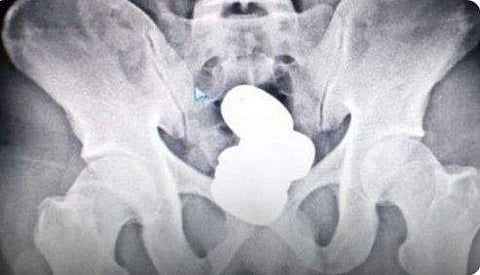

സ്വര്‍ണം മലദ്വാരത്തില്‍ ഒളിപ്പിച്ച നിലയില്‍ / ട്വിറ്റര്‍ ചിത്രം

മലദ്വാരത്തില്‍ നാലു പാക്കറ്റുകളിലാക്കിയാണ് ഇയാള്‍ സ്വര്‍ണം കടത്താന്‍ ശ്രമിച്ചത്. തിങ്കളാഴ്ച ഉച്ചയ്ക്ക് 2.40 നുള്ള ഇംഫാല്‍-ഡല്‍ഹി വിമാനത്തിലാണ് മുഹമ്മദ് ഷരീഫ് യാത്ര ചെയ്യേണ്ടിയിരുന്നത്.

സുരക്ഷാപരിശോധനയ്ക്കിടെ സംശയം തോന്നി ഇയാളെ ചോദ്യം ചെയ്യുകയായിരുന്നു. പരസ്പര വിരുദ്ധ മറുപടി ലഭിച്ചതിനെ തുടര്‍ന്ന് എക്‌സ്‌റേ പരിശോധന നടത്തിയപ്പോഴാണ്, ഒളിപ്പിച്ച നിലയില്‍ സ്വര്‍ണം കണ്ടെത്തിയത്.